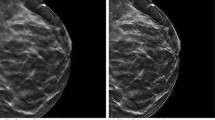

The main objective of the image enhancement is to improve the visual appearance or quality of an image. In this paper, the proposed scheme aims to improve the performance of the homomorphic filtering by employing the fractional derivatives with Discrete Fourier Transform (DFT) and Fractional Fourier Transform (FrFT). FrFT in combination with fractional derivative provides two fractional orders as extra degrees of freedom, thus, providing more design flexibility. This paper uses Grunwald-Letnikov (GL) fractional derivative to enhance the high and mid frequency components non-linearly while preserving the low frequency components. In the proposed approach, modification of homomorphic filtering technique is done on the basis of fractional derivative and FrFT to enhance the low contrast and non-uniformly illuminated images. The effectiveness of the proposed work is evaluated on the basis of various image assessment parameters such as PSNR, information entropy, universal image quality index, etc. on several images of different sizes. The proposed scheme outperforms the existing state-of-the-art techniques by providing better image visual quality and image information in terms of average PSNR and entropy values. The improvement in the average PSNR and information entropy is in the range 0.2635–50.37 dB and 0.02–42% respectively for standard images as well as for images with different contrast and illumination conditions.